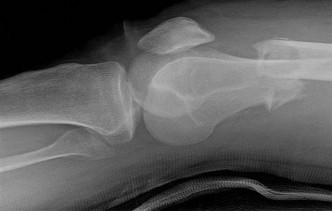

A 30-year-old male sustains an axial load to a plantarflexed foot. On physical examination, there is pronounced plantar ecchymosis and localized pain with passive pronation and abduction of the forefoot.

The primary stabilizing ligament of the disrupted joint complex connects which two osseous structures?

Explanation

Plantar ecchymosis in the midfoot is the pathognomonic sign of a Lisfranc injury. The Lisfranc ligament is an interosseous ligament that represents the strongest and most critical stabilizer of the tarsometatarsal complex. It runs obliquely from the lateral aspect of the medial cuneiform to the medial base of the second metatarsal. There is notably no direct transverse ligamentous connection between the bases of the first and second metatarsals.